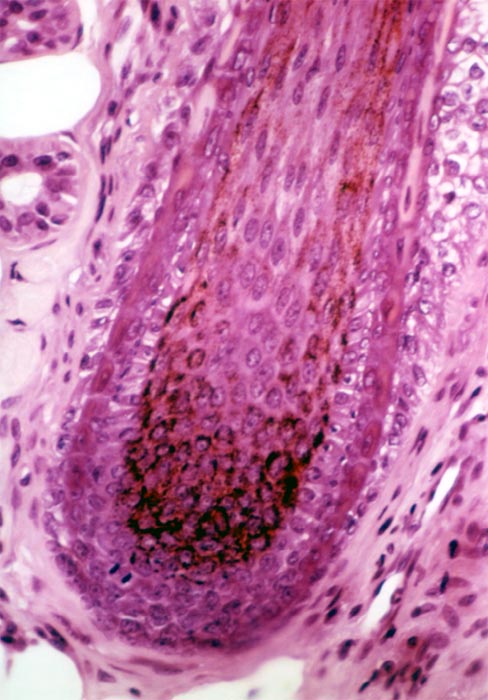

Evaluation of the melanic pigmentation of the hair bulb :

- Analysis of the transfer of melanocytes’ specks of melanin to the bulbous cells of the hair bulb

- Fontana coloration (quantitative scores)